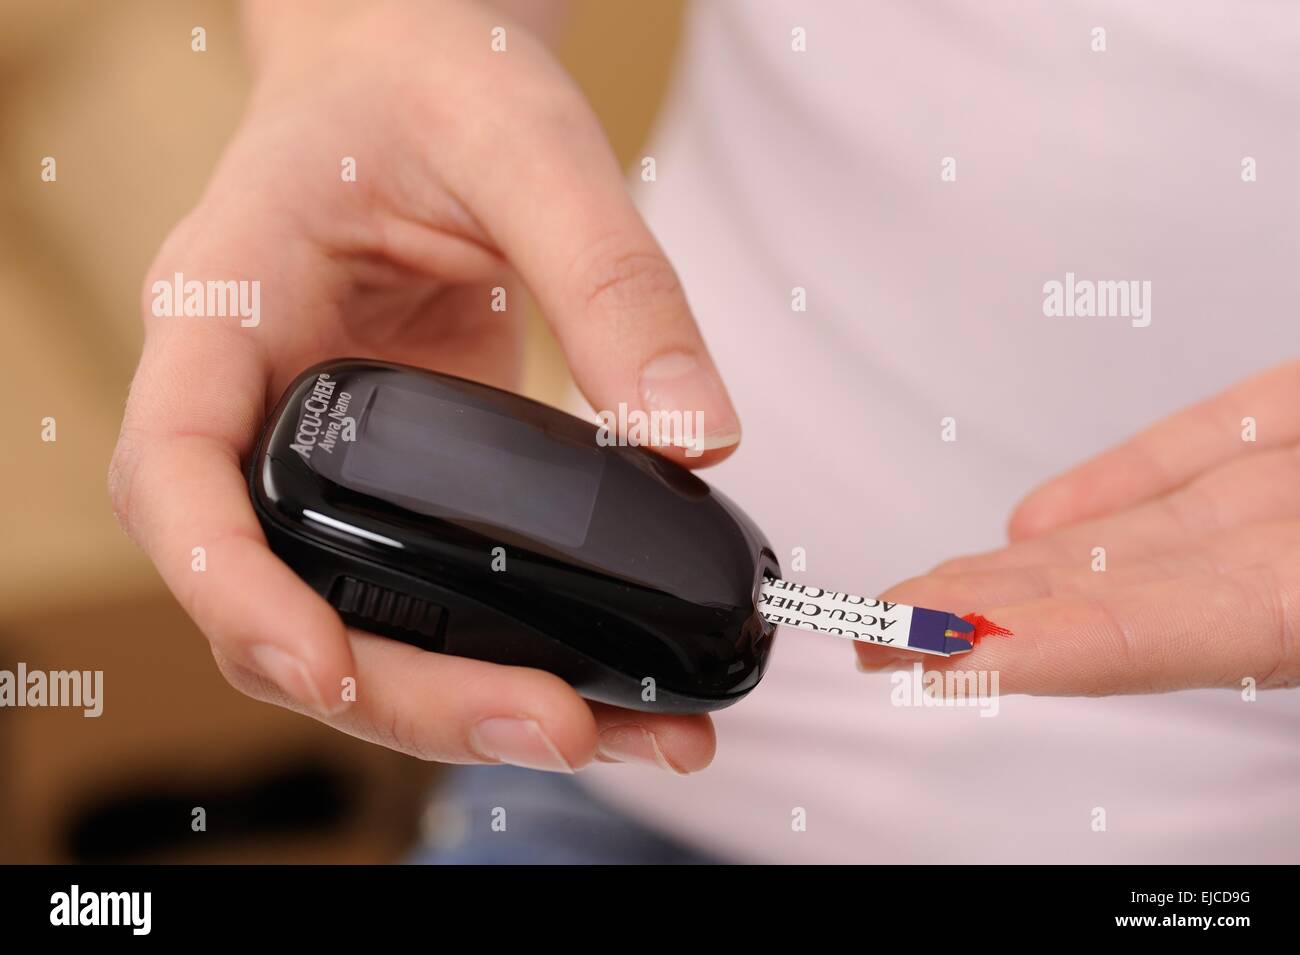

Accu chek avia nano Foto Stockhttps://www.alamy.it/image-license-details/?v=1https://www.alamy.it/foto-immagine-accu-chek-avia-nano-80179165.html

Accu chek avia nano Foto Stockhttps://www.alamy.it/image-license-details/?v=1https://www.alamy.it/foto-immagine-accu-chek-avia-nano-80179165.htmlRMEJCD9H–Accu chek avia nano

Accu chek avia nano Foto Stockhttps://www.alamy.it/image-license-details/?v=1https://www.alamy.it/foto-immagine-accu-chek-avia-nano-80179164.html

Accu chek avia nano Foto Stockhttps://www.alamy.it/image-license-details/?v=1https://www.alamy.it/foto-immagine-accu-chek-avia-nano-80179164.htmlRMEJCD9G–Accu chek avia nano

Accu chek avia nano Foto Stockhttps://www.alamy.it/image-license-details/?v=1https://www.alamy.it/foto-immagine-accu-chek-avia-nano-80179136.html

Accu chek avia nano Foto Stockhttps://www.alamy.it/image-license-details/?v=1https://www.alamy.it/foto-immagine-accu-chek-avia-nano-80179136.htmlRMEJCD8G–Accu chek avia nano

Accu chek avia nano Foto Stockhttps://www.alamy.it/image-license-details/?v=1https://www.alamy.it/foto-immagine-accu-chek-avia-nano-80179160.html

Accu chek avia nano Foto Stockhttps://www.alamy.it/image-license-details/?v=1https://www.alamy.it/foto-immagine-accu-chek-avia-nano-80179160.htmlRMEJCD9C–Accu chek avia nano

Accu chek avia nano Foto Stockhttps://www.alamy.it/image-license-details/?v=1https://www.alamy.it/foto-immagine-accu-chek-avia-nano-80179161.html

Accu chek avia nano Foto Stockhttps://www.alamy.it/image-license-details/?v=1https://www.alamy.it/foto-immagine-accu-chek-avia-nano-80179161.htmlRMEJCD9D–Accu chek avia nano

Accu chek avia nano Foto Stockhttps://www.alamy.it/image-license-details/?v=1https://www.alamy.it/foto-immagine-accu-chek-avia-nano-80179140.html

Accu chek avia nano Foto Stockhttps://www.alamy.it/image-license-details/?v=1https://www.alamy.it/foto-immagine-accu-chek-avia-nano-80179140.htmlRMEJCD8M–Accu chek avia nano

Accu chek avia nano Foto Stockhttps://www.alamy.it/image-license-details/?v=1https://www.alamy.it/foto-immagine-accu-chek-avia-nano-80179152.html

Accu chek avia nano Foto Stockhttps://www.alamy.it/image-license-details/?v=1https://www.alamy.it/foto-immagine-accu-chek-avia-nano-80179152.htmlRMEJCD94–Accu chek avia nano

Accu chek avia nano Foto Stockhttps://www.alamy.it/image-license-details/?v=1https://www.alamy.it/foto-immagine-accu-chek-avia-nano-80179149.html

Accu chek avia nano Foto Stockhttps://www.alamy.it/image-license-details/?v=1https://www.alamy.it/foto-immagine-accu-chek-avia-nano-80179149.htmlRMEJCD91–Accu chek avia nano